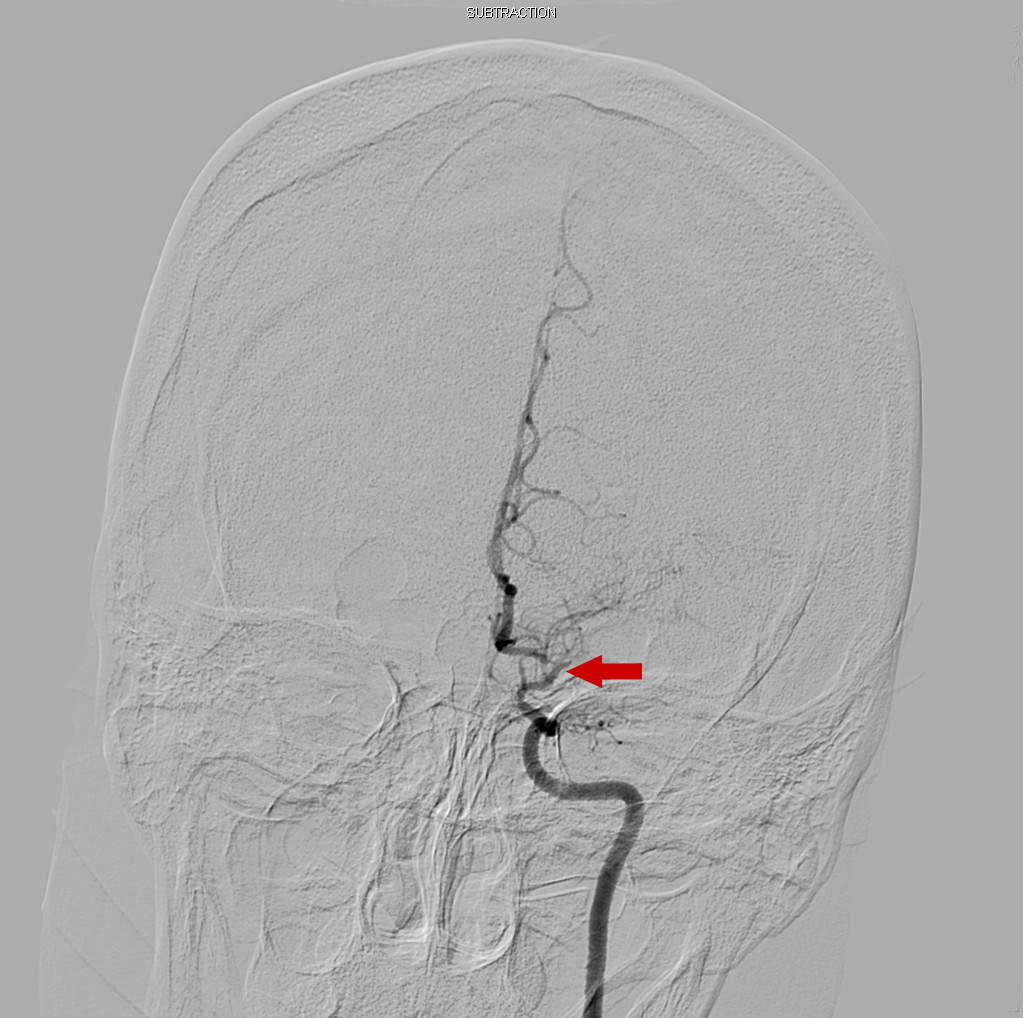

Cerebral angiography was then performed to further clarify the MRI findings; the results showed severe stenosis of the right and left middle cerebral and anterior cerebral arteries (Figure 4).

Figure 4